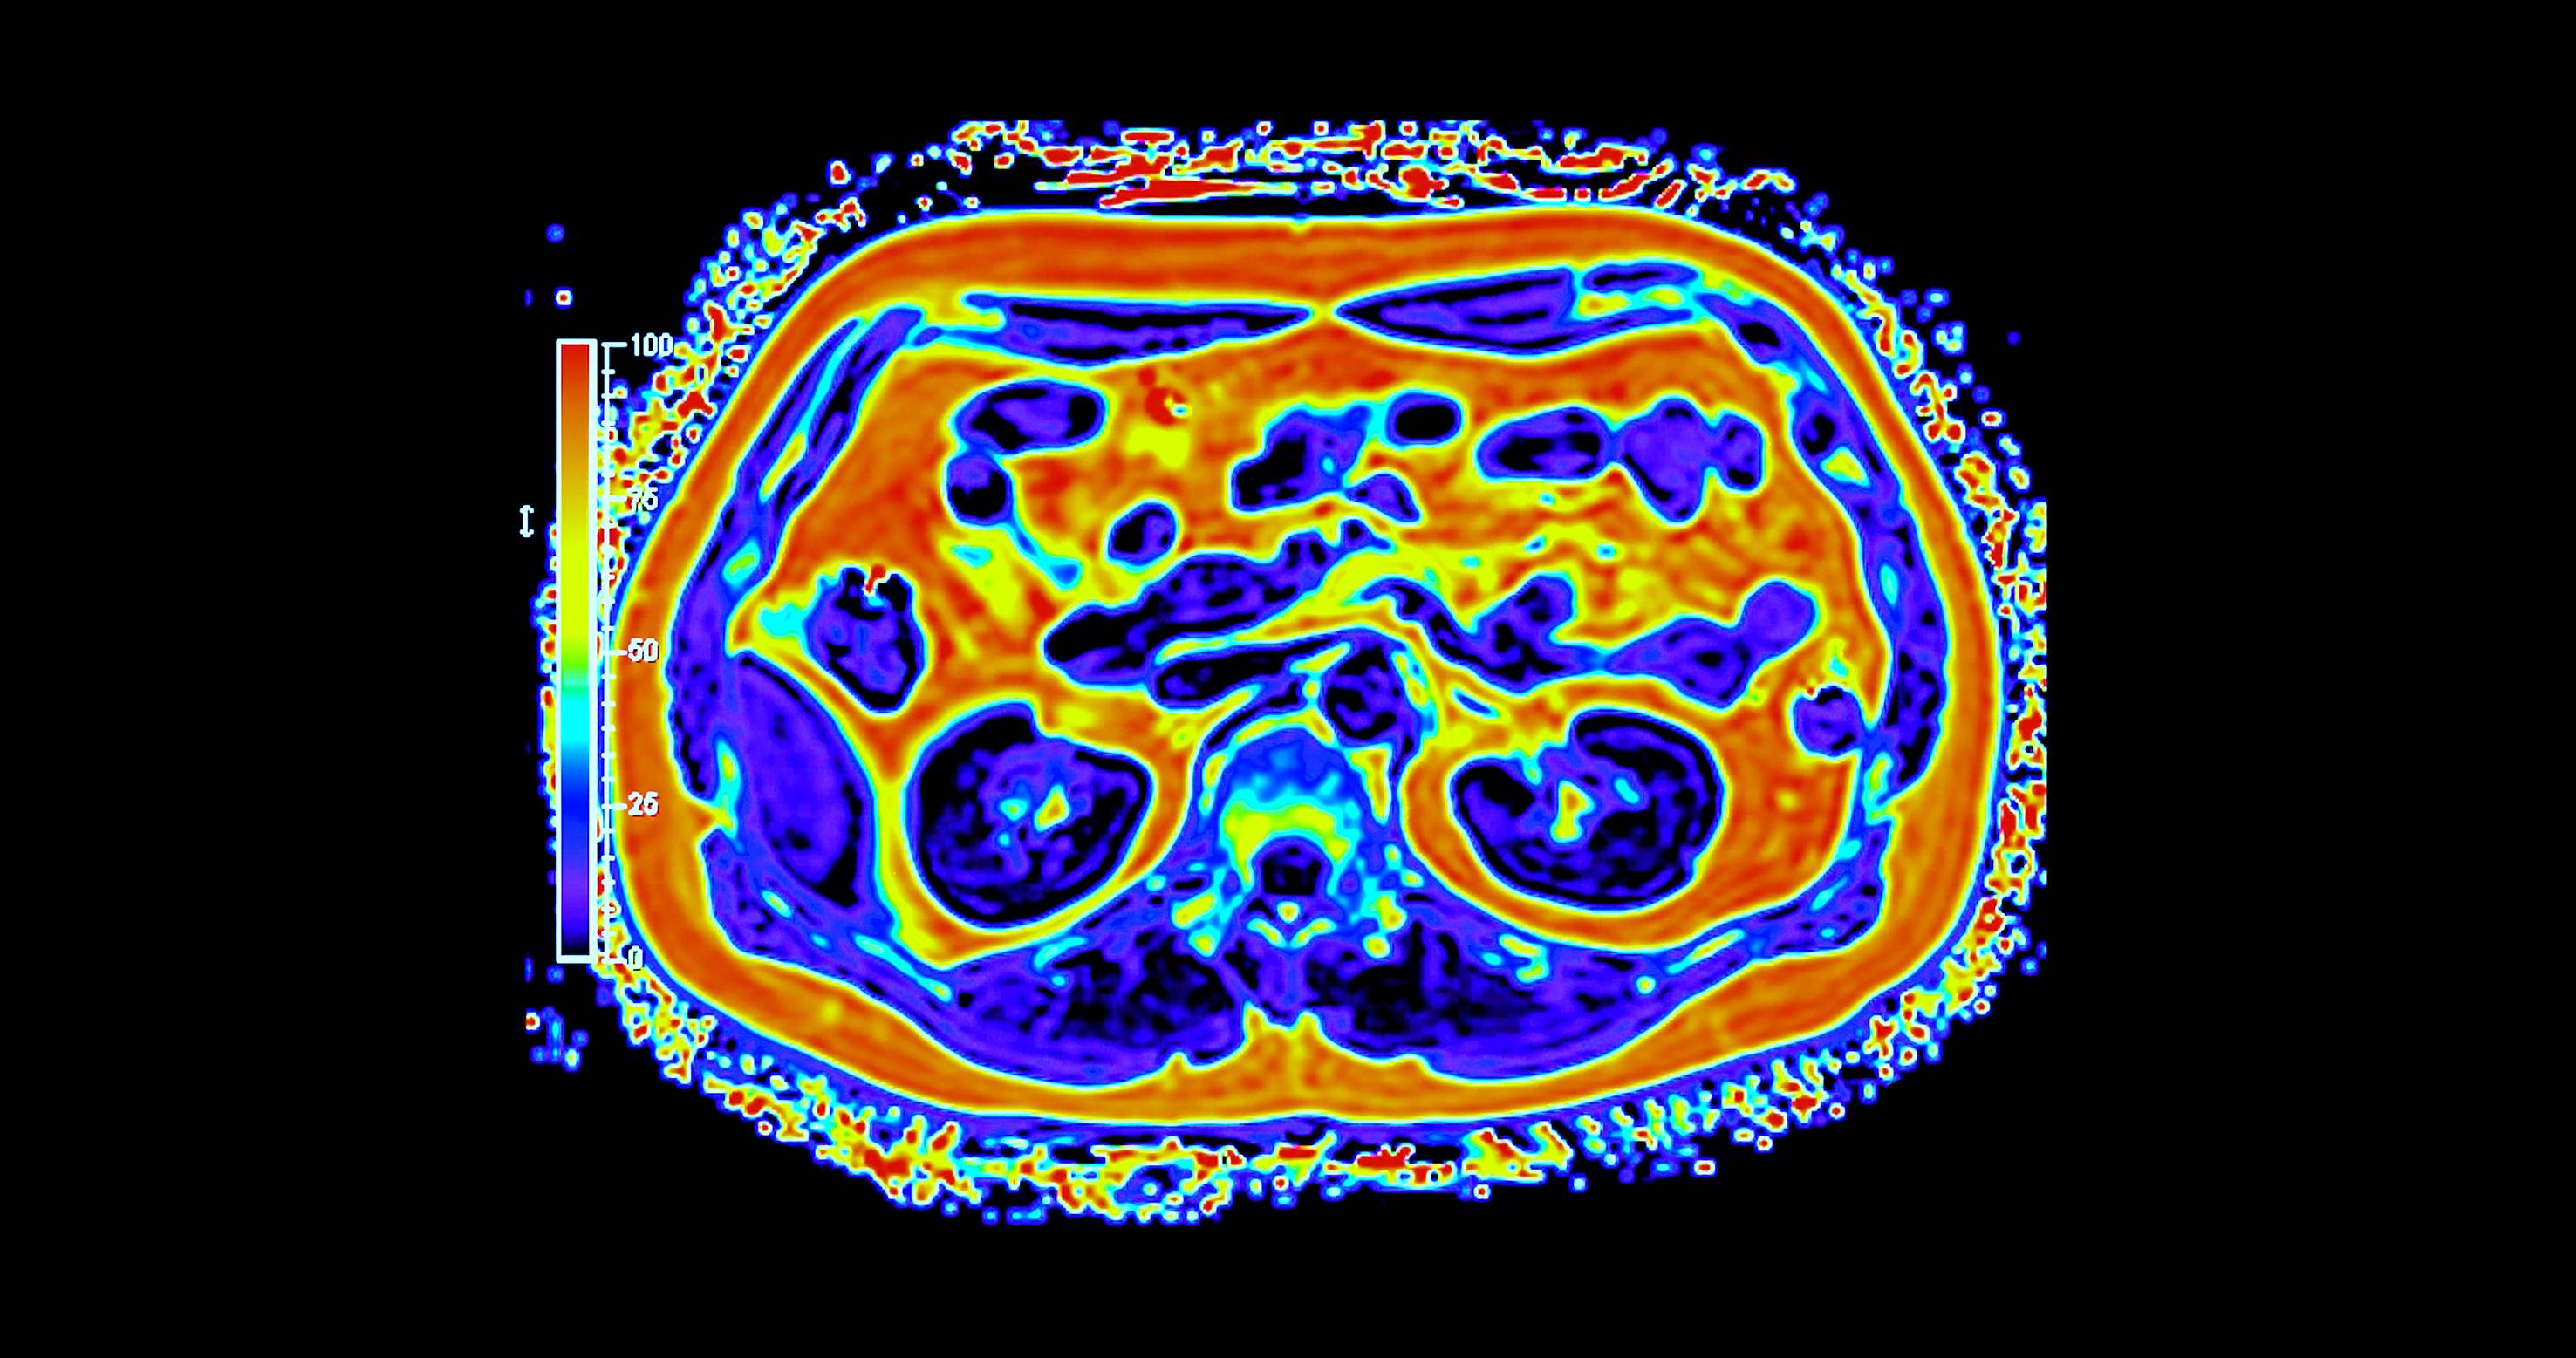

غالباً ما يُتناول تحوّل القطاع الصحي عبر محطات واضحة للعيان، مثل إنشاء مستشفيات جديدة، وإطلاق منصات رقمية، واعتماد أجهزة طبية متقدمة. غير أنّ جانباً أقل ظهوراً وأكثر حسماً يتمثل في بناء بنية تحتية تشخيصية قادرة على دعم الاكتشاف المبكر والطب الدقيق والرعاية الوقائية على نطاق وطني. ويقع التصوير الجزيئي، ولا سيما التقنيات الهجينة، مثل «PET – MRI» في صميم هذا التحول.

وعلى خلاف التصوير التقليدي، يجمع التصوير الجزيئي بين التفاصيل التشريحية والبيانات الوظيفية الآنية، ما يتيح للأطباء رؤية كيفية عمل الأنسجة لا مجرد شكلها. وفي مجالَي الأورام والأمراض العصبية، قد يُحدث هذا الفرق تحولاً في توقيت الاكتشاف أو في تعديل خطط العلاج أو في تجنّب إجراءات غير ضرورية. غير أن توسيع هذه القدرات عبر بلد واسع ومتنوّع جغرافياً يطرح تحديات تتجاوز كثيراً مجرد اقتناء الأجهزة.